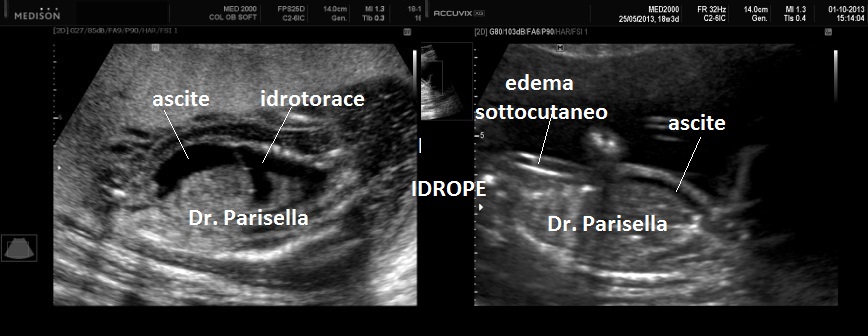

Possono essere presenti: idrope, cardioaptie congenite, labiopalatoschisi, oligoamnios, anomalie genito-urinarie, anomalie gastro-intestinali, anomalie del SNC.

La MICROMELIA SEVERA e l’ IPOPLASIA TORACICA SEVERA (legata al torace stretto con coste corte) sono i segni principali che indirizzano verso una corretta diagnosi. La POLIDATTILIA, sempre presente, è di tipo postassiale ed interessa sia mani che piedi. Spesso è presente idrope.

Sono presenti labiopalatoschisi, anomalie genitourinarie ed anomalie gastrointestinali. Può essere presente idrope ed ascite.

5)    L’ idrope può essere presente nei tipi I e IV.